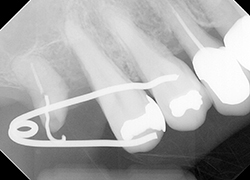

【治療前】

右上6番(第1大臼歯)の3根の内の1本だけが残存して5番(第2小臼歯)にぶつかってしまっています。

このままだと接触点が上手く磨けないため、5番までが虫歯になってしまいます。

通常ならこのまま抜歯で、抜歯後をどうするかという相談になるかと思いますが、6番(第1大臼歯)の3根中、2根ないし1根だけでも補綴治療をして温存している症例があるのも事実です。

【治療中】

特殊な部分矯正装置を用いて、アップライト(引き起こし)を試みました。